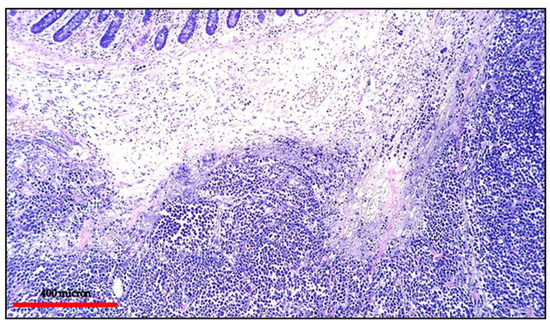

BL typically consists of a diffuse cohesive proliferation of monomorphic medium-sized cells with round nuclei, finely clumped chromatin and multiple small nucleoli. The cytoplasm is deeply basophilic and contains lipid vacuoles more easily seen in imprint preparations (Figure 10).

Figure 10.

(A) BL of the duodenum: lymphoid infiltrate within the duodenal mucosa (Hematoxylin and eosin, magnification 200×; original image from Prof Ascani); (B) BL: diffuse CD20 positivity confirming the B-cell phenotype of the lymphoid cells (immunostaining, Ventana immunostainer, magnification 100×; original image from Prof Ascani).

Frequent mitotic figures and apoptosis are present; the starry sky pattern is indicative of the high proliferative index and is due to the presence of numerous tingible-body macrophages.

BL cells have a full B-cell phenotype with strong positivity for CD20, CD79alpha, PAX5, CD19 and IgM expression with light chain restriction. The cells express germinal center markers (CD10 and BCL6) and are usually negative for BCL2. In some cases, there is an atypical phenotype with the absence of CD10, CD5 positivity and weak BCL2 expression. The proliferation rate is very high (ki67 > 95%) and there is strong MYC protein overexpression. EBER is positive (Figure 11) in the majority of endemic BL and only in a subset of sporadic and immunodeficiency-associated cases [8].

Figure 11.

(A) BL of the duodenum: diffuse EBV expression by in situ hybridization (EBER-ISH, magnification 200×; original image from Prof Ascani); (B) BL of the duodenum: diffuse MYC protein overexpression of the lymphoid cells (immunostaining, Ventana immunostainer, magnification 200× original image from Prof Ascani).